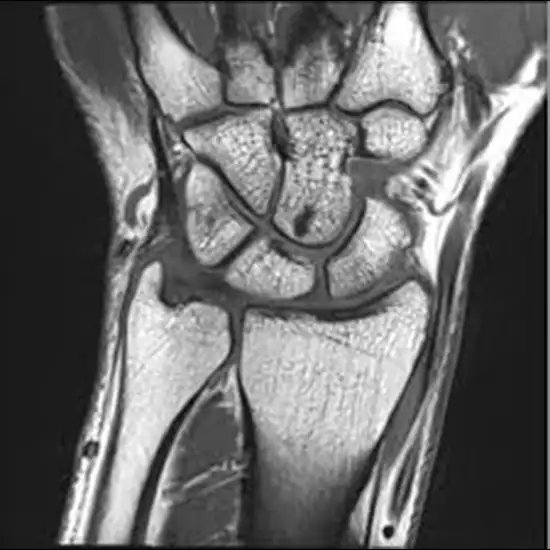

What is MRI Wrist Bilateral With Contrast Test?

MRI of the wrist allows doctors to examine the anatomy of the wrist and rule out any structural abnormalities.

In this test both wrists will be examined by your doctor.